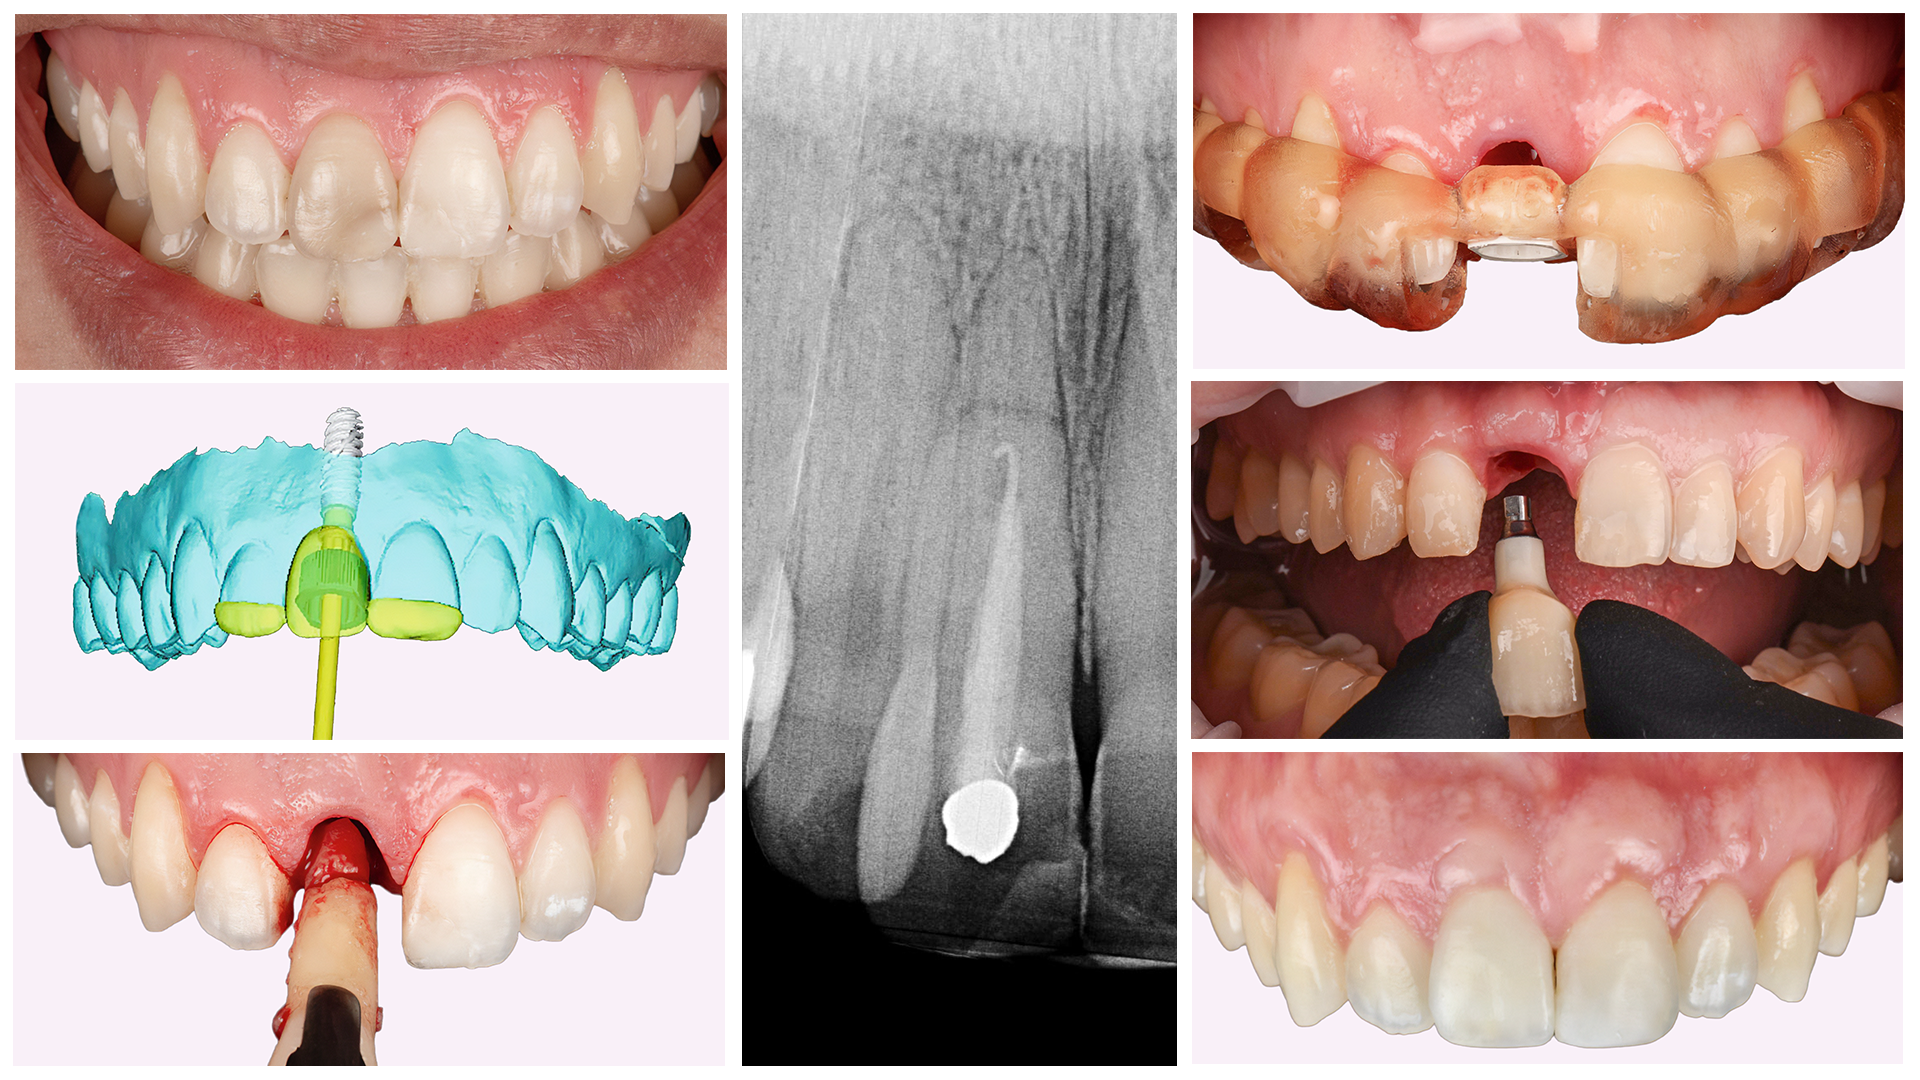

Імплантація — це встановлення штучного кореня зуба (імплантата) на місце втраченого. Цей процес включає кілька етапів: планування, хірургічне втручання і, неймовірно, але факт, відновлення. Прекрасна естетика та висока функціональність у поєднанні з надійністю та тривалістю! Прямо сказати, це ідеальне рішення в умовах сучасного життя.

Імплантація зубів — це як великий пазл, кожна частина якого виконана з досконалою точністю. Все починається з хірургічного втручання, під час якого імплантат встановлюється у кістку щелепи. Потім дається час на остеоінтеграцію — цей складний процес, коли імплантат зростається з кісткою, може тривати від кількох тижнів до місяців.

Наступний етап — це встановлення абатмента, до якого закріплюється коронка. Ось і все, новий зуб готовий служити вам вірою та правдою.